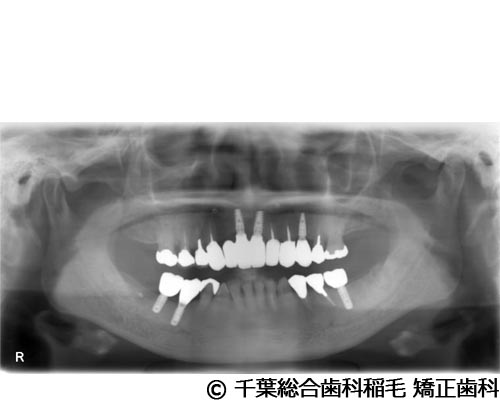

【症例5】All-on-6(オールオン6)

- 治療前

- 治療後

- 治療名

- All-on-6(オールオン6)

- 費用

- 7,500,000円(税込)

- 期間

- 10ヵ月

治療内容

-

患者様の症状

入れ歯が合わなくなり、お食事も満足にできないとご来院されました。

治療法

ご相談の結果、上顎はインプラントを6本、下顎は7本埋入し、All-on-6(オールオン6)という固定式のインプラント治療を行いました。

治療結果

入れ歯が動いてしまう煩わしさがなくなり、よく噛めるようになったと仰っています。

※治療結果は患者様によって個人差があります。